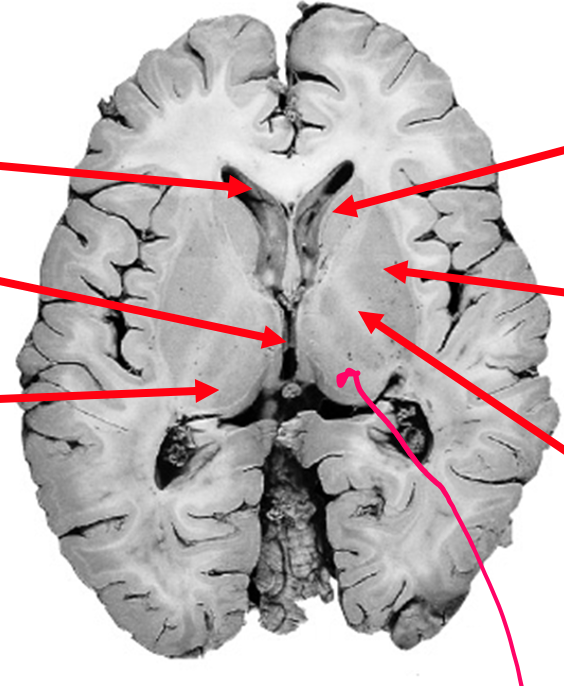

What is the caudate nuceli?

Collection of neuronal cell bodies within the cerebral hemisphere

Label the ventricles of the brain & the parts of the basal glanglia